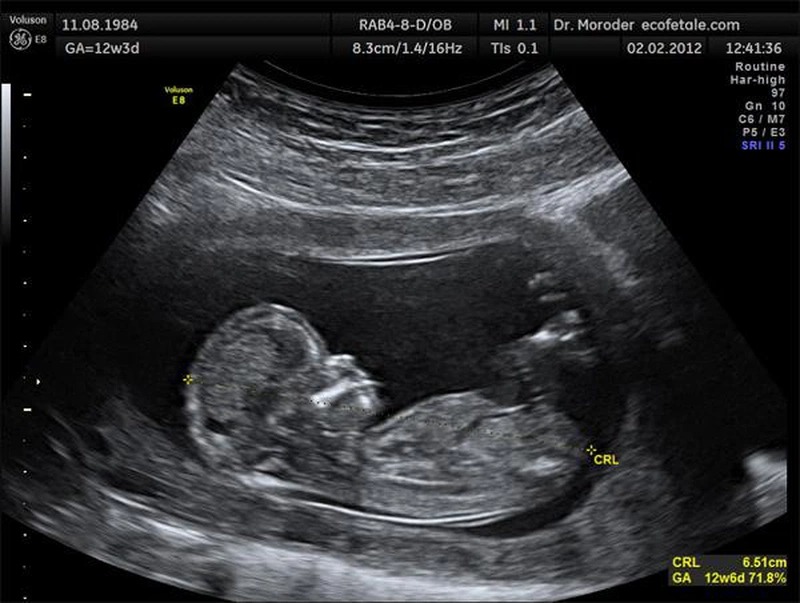

Đối với thai nhi 22 tuần, chiều dài xương mũi thường được đo và so sánh với các tiêu chuẩn được xác định bởi các tổ chức, chuyên gia y tế. Thực tế, chiều dài xương mũi của thai nhi sẽ tăng dần lên 6,00 - 6,65mm từ tuần 23 đến tuần 26 của thai kỳ. Chính vì vậy, thông thường chiều dài xương mũi tiêu chuẩn của thai nhi 22 tuần sẽ khoảng 6mm.

Tuy nhiên, hãy lưu ý, chiều dài xương mũi của thai nhi sẽ có sự khác biệt tùy vào thể trạng của mẹ, gen di truyền hay các yếu tố khác. Vì vậy con số trên chỉ là một con số để các bậc cha mẹ tham khảo. Để có thể xác định chính xác chiều dài xương mũi thai nhi 22 tuần có bình thường hay không, hãy tham khảo ý kiến của các chuyên gia y tế.